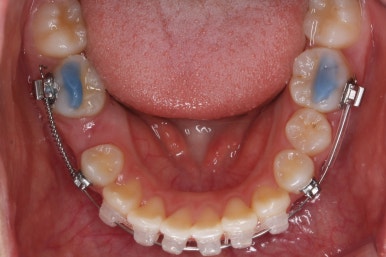

부산치아교정잘하는곳 처음 오셨을 때의 입안 모습입니다.

맨 우측 밑에 사진을 보시면 이가 하나 더 나와야 할 자리에(화살표) 앞뒤로 치아가 쓰러지면서 자리를 거의 없애버렸습니다.

따라서 이가 나올래야 나올 수가 없는 상태였습니다.

왼쪽 맨 위 사진을 보시면 아래 치열의 중앙이 한 쪽으로 쏠린 것을 알 수 있는데요. 역시 치아가 나올 자리가 없어지면서 치열이 쏠러버렸다는 것을 알 수 있습니다.